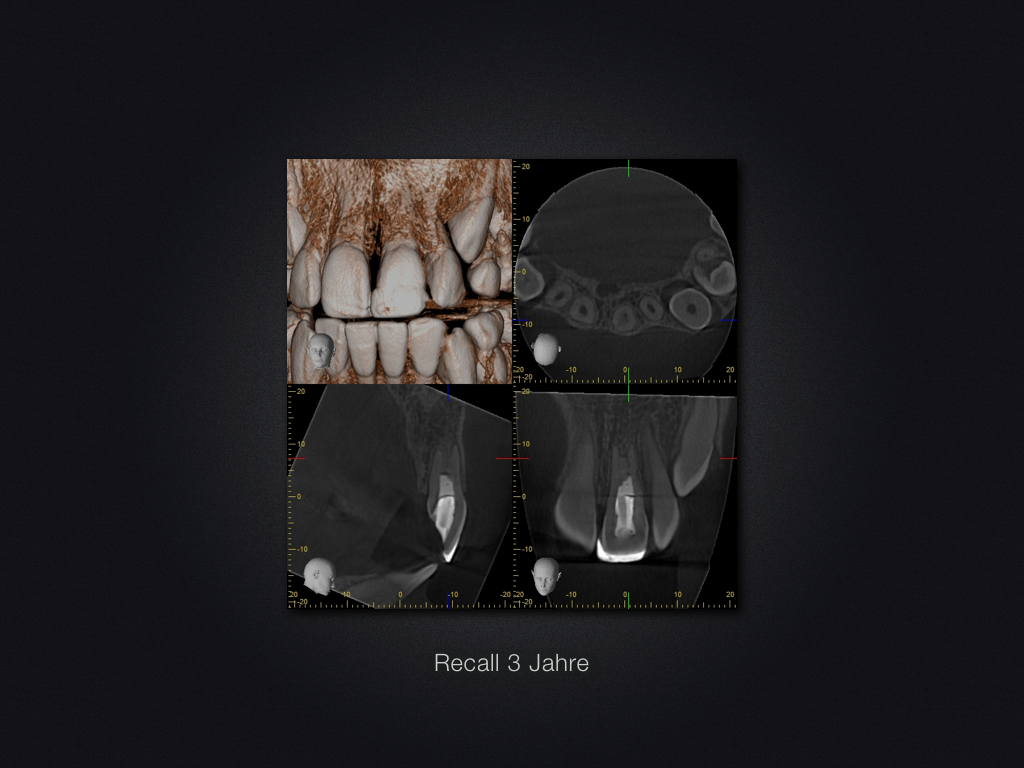

Praxistauglicher Kompromiss